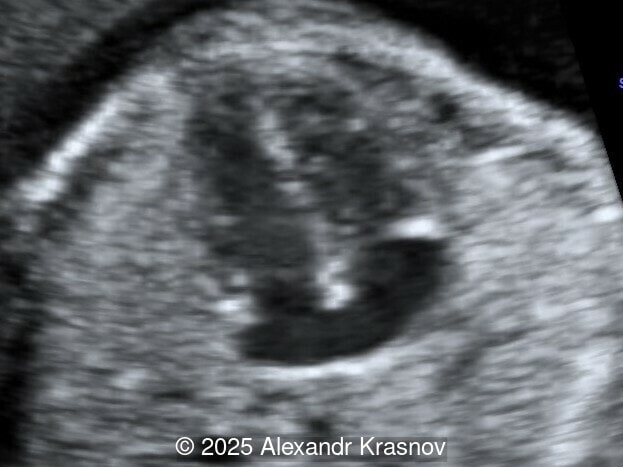

Image 1

Our ultrasound showed biometry data corresponding to 21 weeks of gestation. During echocardiography, an abnormal drainage of the pulmonary veins was detected in which the pulmonary veins drain into a venous collector linked to the superior vena cava. The four-chamber view and the three-vessel view were altered and raised suspicion of a pathology. The grayscale and color Doppler images of the four-chamber view indicate a smooth posterior wall of the left atrium, increased distance between the left atrium and the descending aorta and the absence of pulmonary veins entering the left atrium (Image 1, 2; Video 1, 2). In the three-vessel view, the diameter of the superior vena cava appears larger than that of the aorta (Image 3, Video 3). In the images of the venae cava, a significant difference is seen between the diameters of the inferior and superior vena cava with significant enlargement of the superior vena cava (Image 4, Video 4). Additionally, there is a pulmonary venous confluent chamber (“twig sign”) behind the left atrium (Image and Video 5). A vertical ascending vein connects the confluent chamber with the superior vena cava where it drains blood from the pulmonary veins (Images 6, 7; Video 6).